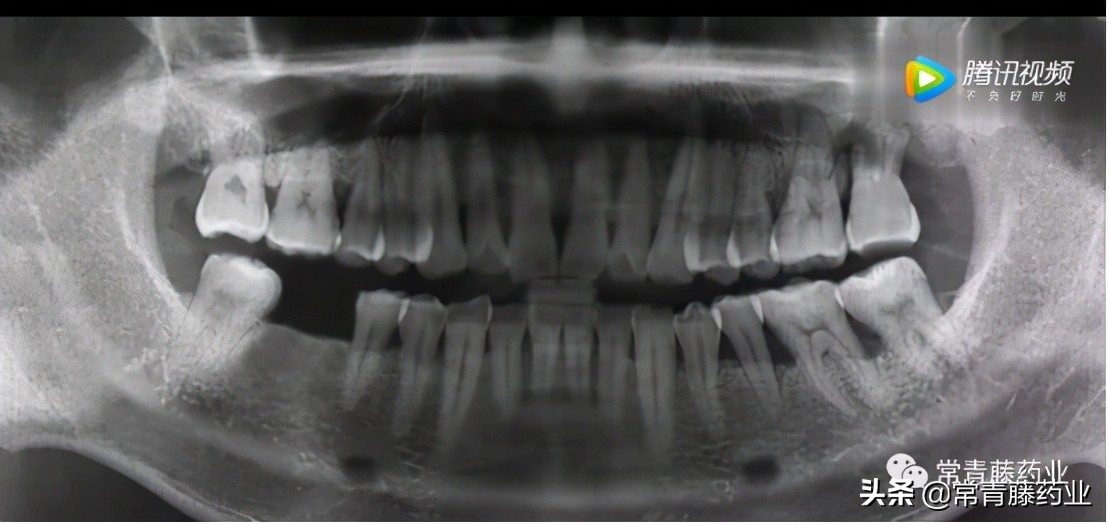

在种牙开始之前需要进行口腔检查和全景片、颌骨CT拍摄以确定牙周是否有炎症、牙槽骨头是否拥挤以及牙体情况等。(如下图)